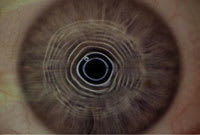

| Figure 2. Photokeratoscopy OS, note the distortion of the center five rings. |

In 2000 KW began wearing a custom daily wear soft lens (+8.50D) OD with good success and a functional VA of 20/25. With his traditional toric soft lens on the left eye, his VA was 20/50 and he complained of significant distortion at distance and near as well as of glare and halos at night. Figure 2 shows the patient's photokeratoscopy OS  note the distortion and uneven spacing between the center five rings.